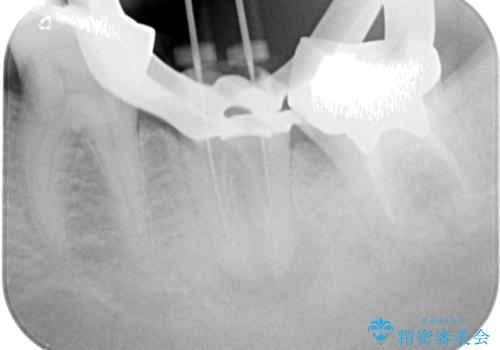

診察の結果、既に根管治療をされている第二大臼歯の根尖部に大きな病変があり、それが痛みの原因であるため、根管治療が必要と判断されました。

根管治療後6か月が経過してレントゲンを撮影したところ、非常に大きかった病変が小さくなっていることが確認されました。